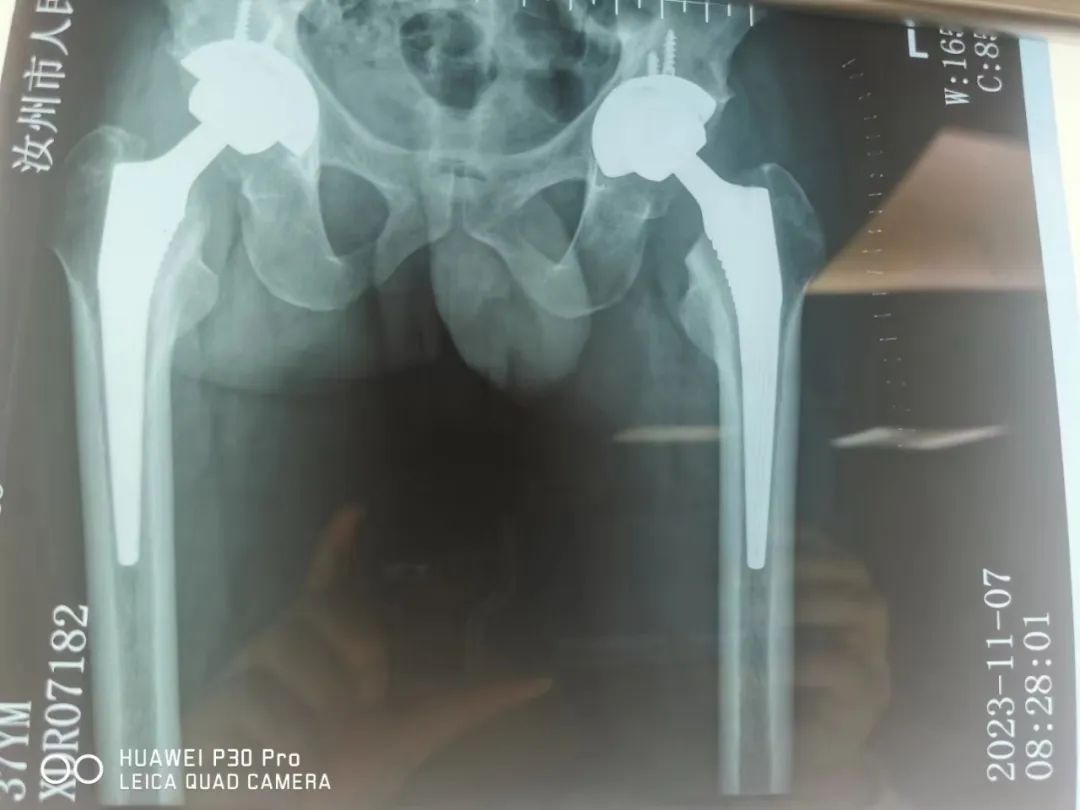

髋关节置换后影像

集采人工髋关节让患者获益